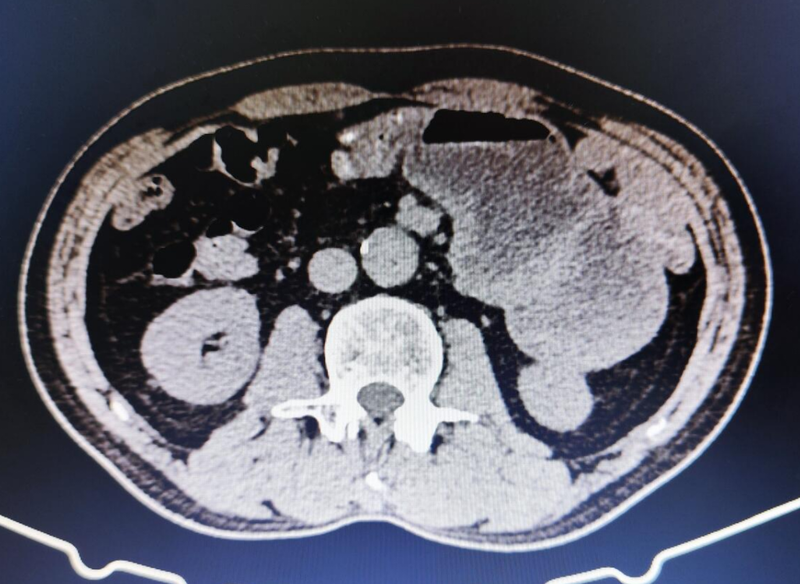

近日,筆者接診了一例“腹痛”患者。術(shù)前檢查發(fā)現(xiàn)空腸梗阻(圖一),近段空腸疝入網(wǎng)膜囊(圖二),結(jié)腸異位(圖三)??紤]腸旋轉(zhuǎn)不良導(dǎo)致空腸扭轉(zhuǎn)、腹內(nèi)疝。為避免空腸壞死,與患者及家屬溝通病情后,急診全麻下施術(shù),術(shù)中見盲腸位于臍部(圖四),與空腸近段完全粘連(圖五)??漳c扭曲,疝入小網(wǎng)膜囊。遂行“經(jīng)腹腔鏡Ladd術(shù)”,術(shù)中分離盲腸粘連,找到并切斷Ladd纖維帶(圖六),復(fù)位空腸,切除異位闌尾,手術(shù)完全在腹腔鏡下完成(圖七)。術(shù)后2天患者通氣,逐步恢復(fù)飲食,恢復(fù)良好,1周出院??破眨耗c旋轉(zhuǎn)異常(malrotationofintestine)是胚胎時期以腸系膜上動脈為軸心的腸旋轉(zhuǎn)運動發(fā)生障礙,隨后遺留下腸道解剖位置及其系膜固定異常,引起的一些外科性疾病。臨床上常見到的外科疾病可歸納為三種:①中腸扭轉(zhuǎn);②十二指腸梗阻;③內(nèi)疝。Ladd手術(shù)是治療本病的經(jīng)典方法,手術(shù)的關(guān)鍵點在于復(fù)位扭轉(zhuǎn)中腸,松解Ladd束帶。傳統(tǒng)Ladd手術(shù)開腹下進(jìn)行,手術(shù)創(chuàng)傷大,術(shù)后恢復(fù)慢,我科開展“經(jīng)腹腔鏡Ladd術(shù)”創(chuàng)傷小,傷口美觀且無切口裂開并發(fā)癥,術(shù)后恢復(fù)快。